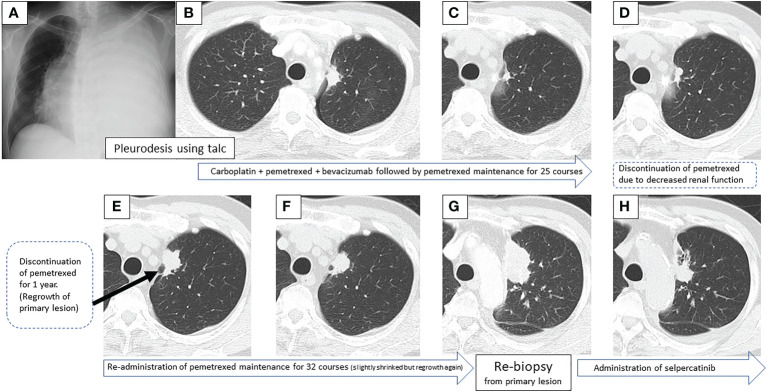

图1:在第一次就诊到开始进行第二次治疗期间,患者7年间原发病灶的顺序图像

一线治疗包括卡铂+培美曲塞+贝伐单抗,经过4个疗程后获得近乎完全缓解(CR),但鼻出血仍然持续,仅进行培美曲塞维持治疗。在维持治疗的25个疗程中实现了CR(图1C),但由于肾功能轻微恶化,治疗暂时中断。治疗结束后一年,CT显示原发病灶轻微进展(图1D),但复发速度较慢。确认CT复发一年后(图1E),重新开始培美曲塞单药治疗,原发病灶和淋巴结减小(图1F)。然而,在进行了32个维持治疗疗程后,出现了快速的全身进展。由于原发病灶再生(图1G)、对侧肺转移、多发性肝转移、右侧肾上腺转移和多发性脑转移(图2A、B),需要调整他的治疗方案。